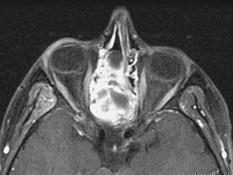

15岁,男性,渐进性鼻塞1年余,MRI扫描如图所示,请选择最可能诊断 ( )

• A.鼻咽部脓肿

• B.鼻咽部纤维血管瘤

• C.脊索瘤

• D.鼻咽癌

• E.鼻咽部囊肿

答案: B